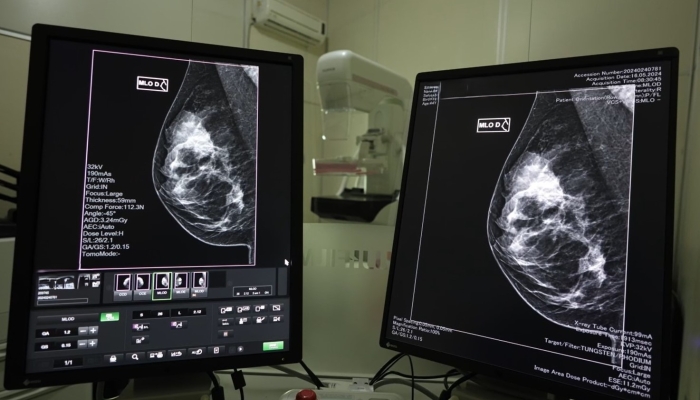

Hospitais de gestão estadual que prestam serviços de saúde da mulher e possuem mamógrafos também realizam os exames - Foto: Divulgação

As mamografias são realizadas pelo SUS, via Atenção Primária à Saúde, com prestadores dos municípios e Consórcios de Saúde.

Hospitais de gestão estadual que prestam serviços de saúde da mulher e possuem mamógrafos também realizam os exames.